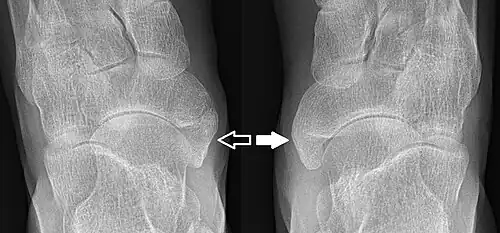

- Type 2 on one foot (dark arrow) and type 3 on the other (white arrow)